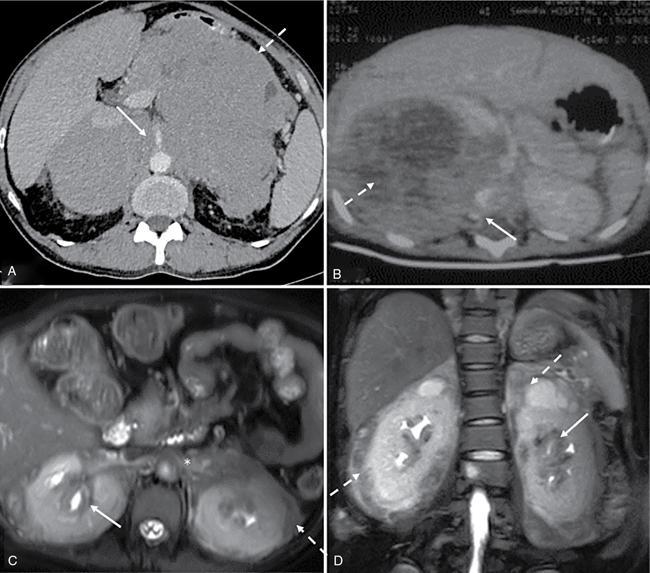

Devasenathipathy Kandasamy, Naren Hemachandran Retroperitoneal masses in children are relatively rare tumours and can primarily arise from the retroperitoneum or from any of the retroperitoneal organs (kidneys, adrenals, pancreas, duodenum, ascending and descending colon). This chapter primarily focuses on the primary retroperitoneal and adrenal masses. The spectrum of tumours affecting the paediatric age group is considerably different from those seen in the adults. The wide spectrum of diseases results in a wide range of clinical presentations which range from totally asymptomatic to even neurological symptoms in some. The presentation is usually nonspecific and imaging plays a major role in identification and characterization of these lesions. Ultrasonography is the initial modality used in children with any abdominal symptoms. Ultrasonography primarily serves three purposes. Firstly, as a screening tool for the detection of these masses, which would then be further evaluated with Computed Tomography (CT) or Magnetic Resonance Imaging (MRI), and secondly for characterizing whether a mass is cystic or solid and thirdly to localize it. CT is the workhorse in the evaluation, localization and characterization of retroperitoneal masses in children. Due to short scan times and a high spatial resolution, CT is the preferred modality in children with retroperitoneal masses. MRI in children usually requires deep sedation or general anaesthesia due to the longer acquisition time. Thus, in spite of a better contrast resolution, MRI is only used as a problem-solving tool. In this chapter, we propose a radiological algorithm for the characterization of various retroperitoneal masses in children. This is based on the primary nature of the mass and they are classified into fat containing, predominantly solid and predominantly cystic groups (Fig. 10.10.1). Various diseases have been categorized into these groups based on the most typical findings. Although not absolute, this radiological algorithm would provide a practical approach to narrow down the differential diagnosis in a child with a retroperitoneal mass. The identification of fat within a lesion considerably narrows down the differentials. The identification of intralesion fat is more easily accomplished on CT/MRI than on ultrasonography. The most common fat containing retroperitoneal lesions in a child are teratoma and lipoblastoma. Teratomas are usually complex solid cystic masses with fat and calcifications, while lipoblastomas are predominantly fat containing masses with variable amounts of enhancing soft tissue. Teratomas are the most common type of germ cell tumours in children. They can be mature, immature and mixed malignant types. Of these, benign mature teratomas are the most common and they show the presence of derivatives of all three embryonic layers – ectoderm, mesoderm and endoderm. They usually present as a painless increase in abdominal girth with a palpable abdominal lump. Imaging shows a heterogeneous solid-cystic mass with variable amount of fat and calcifications. The calcifications are coarse, chunky and well-formed bony components such as teeth are characteristic. Immature teratomas are larger, heterogeneous with or without significant fat component. Presence of haemorrhage or necrosis in a predominantly solid mass is suggestive of malignancy. Benign lesions show mass effect and displacement of the adjacent structures while invasion is typically seen in malignant ones. Other germ cell tumours are seminomatous and nonseminomatous germ cell tumours which include embryonal carcinoma, choriocarcinoma and yolk sac tumour. Primary retroperitoneal germ cell tumours (apart from teratomas) are very rare and majority of them are nodal deposits seen in a patient with a primary gonadal germ cell tumour. These are benign tumours of fatty origin (adipocytes) seen predominantly in infants and children. Lipoblastomas are well delineated, circumscribed, encapsulated lesions while lipoblastomatosis are unencapsulated locally invasive lesions. On imaging, they are almost entirely fatty with variable amounts of enhancing soft tissue components within. This group constitutes the most common retroperitoneal lesions in children. They can be subclassified into those that are diffusely infiltrative and those that are well circumscribed/encapsulated. The former includes neuroblastoma, rhabdomyosarcoma, lymphoma and IgG4 deposition disease while the latter includes ganglioneuroma, adrenocortical carcinoma, neurofibroma and phaeochromocytoma/paraganglioma. Neurogenic tumours can be classified into those of ganglion cell origin (sympathetic and parasympathetic) and those of nerve sheath origin. Tumours of sympathetic ganglion cell origin include ganglioneuroma, ganglioneuroblastoma and neuroblastoma in the increasing order of malignant potential. Tumours of nerve sheath origin can be benign or malignant. Benign nerve sheath tumours include neurofibroma and schwannoma, while their malignant counterpart is malignant peripheral nerve sheath tumour. Of these, neuroblastoma and ganglioneuroblastoma show overlapping clinical and radiological features and are described together here. Those lesions, which are the benign end of the spectrum (ganglioneuroma, schwannoma and neurofibroma), usually present as well-circumscribed lesions and are described in the next section. Neuroblastoma is the most common and the most malignant amongst the spectrum of neurogenic tumours of sympathetic ganglion cell origin. Overall, they represent the fourth most common paediatric malignancy after leukemia, CNS neoplasms and lymphoma. It is usually diagnosed below the age of 5 years (median age of diagnosis – around 16 months). Rarely they can also be diagnosed in-utero on ultrasonography or even in children above the age of 10 years. They can present with a wide range of symptoms and the degrees of symptoms are not related to the size of the tumour. The most common sites of origin of neuroblastoma are adrenal medulla (35%), primary retroperitoneum (30%) followed by posterior mediastinum (20%), pelvis/presacral space (2%–3%) and neck (1%–2%). Nearly half to two-thirds of the patients have disseminated disease at the time of diagnosis with metastasis to bone, liver, lymph nodes or skin. Primary multifocal neuroblastoma is rare and may be familial. They can be synchronous or metachronous noncontiguous tumours. On imaging, these are usually seen as large heterogeneous, diffusely infiltrative, lobulated masses with calcifications in nearly 90% of abdominal neuroblastomas. Heterogeneity is due to areas of necrosis and haemorrhage within the lesion. The lesion lacks a definite capsule and this accounts for its diffusely infiltrative nature, although relatively well-defined masses are not uncommon. Multiple large bulky nodes can be seen with characteristics similar to the primary tumour and this makes the differentiation of the tumour from the adjacent nodal mass difficult. There can be encasement of the vessels without luminal invasion. They typically insinuate around the major vessels and lift the aorta off the vertebral column. Adjacent organs like kidneys are usually displaced by the mass effect. However, they can also show direct invasion of adjacent organs and structures like psoas muscle. Intraspinal extension can be seen and is more often seen in thoracic neuroblastoma than with abdominal neuroblastoma. The International Neuroblastoma Staging System (INSS), first proposed in 1988 and modified in 1993, is still widely used (Table 10.10.1). However, it is based on the extent of tumour removal on surgery and hence cannot be used as a pretreatment staging system.

Predominantly solid lesions – diffusely infiltrative (Figs. 10.10.3 and 10.10.4)

Neuroblastoma